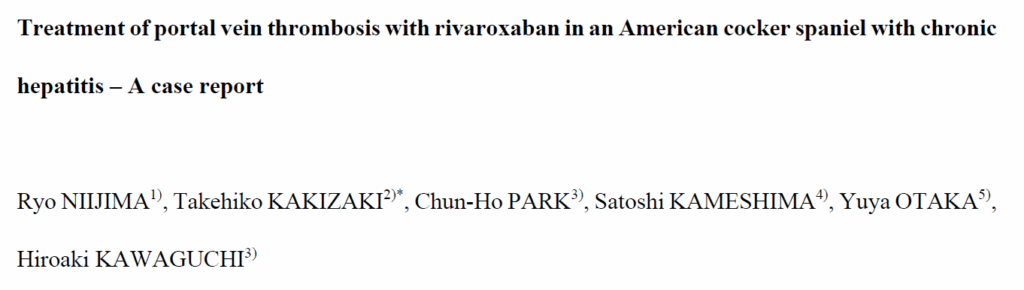

腹部放射影像学检查显示肝脏变小。腹部超声提示肝实质粗糙,左肾后侧有多发性门体分流,脾静脉扩张并伴有血流减少,即脾静脉血栓形成(SVT)(下图A)。腹部超声还提示门静脉血栓形成(PVT)。然而,由于担心病情恶化,未能进行详细的腹部超声以评估门脉,因此未能确诊PVT。观察到少量腹水。超声心动图排除了右心衰竭。

↑ 超声检查结果显示血栓。(A) 在第0天观察到脾静脉扩张和血栓(白色箭头头)。